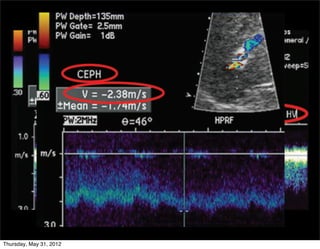

Flujo hepatofugo

• Definición: Flujo que se ALEJA del hígado

Importante en:

1. Diagnóstico HP

2. Conocer permeabilidad de

shunt portosistémico

3. Px hepatópatas

4. Seleccionar pacientes NO

candidatos a

• Quimioembolización

intraarterial

• Portografía arterial por

TC

incich/grupo ct scanner                       Departamento de Radiología/Unidad PET-CT

SIEMPRE demostrar en la misma

• Portografía arterial por   imagen el flujo petal de la arteria

TC                               con el fugo portal